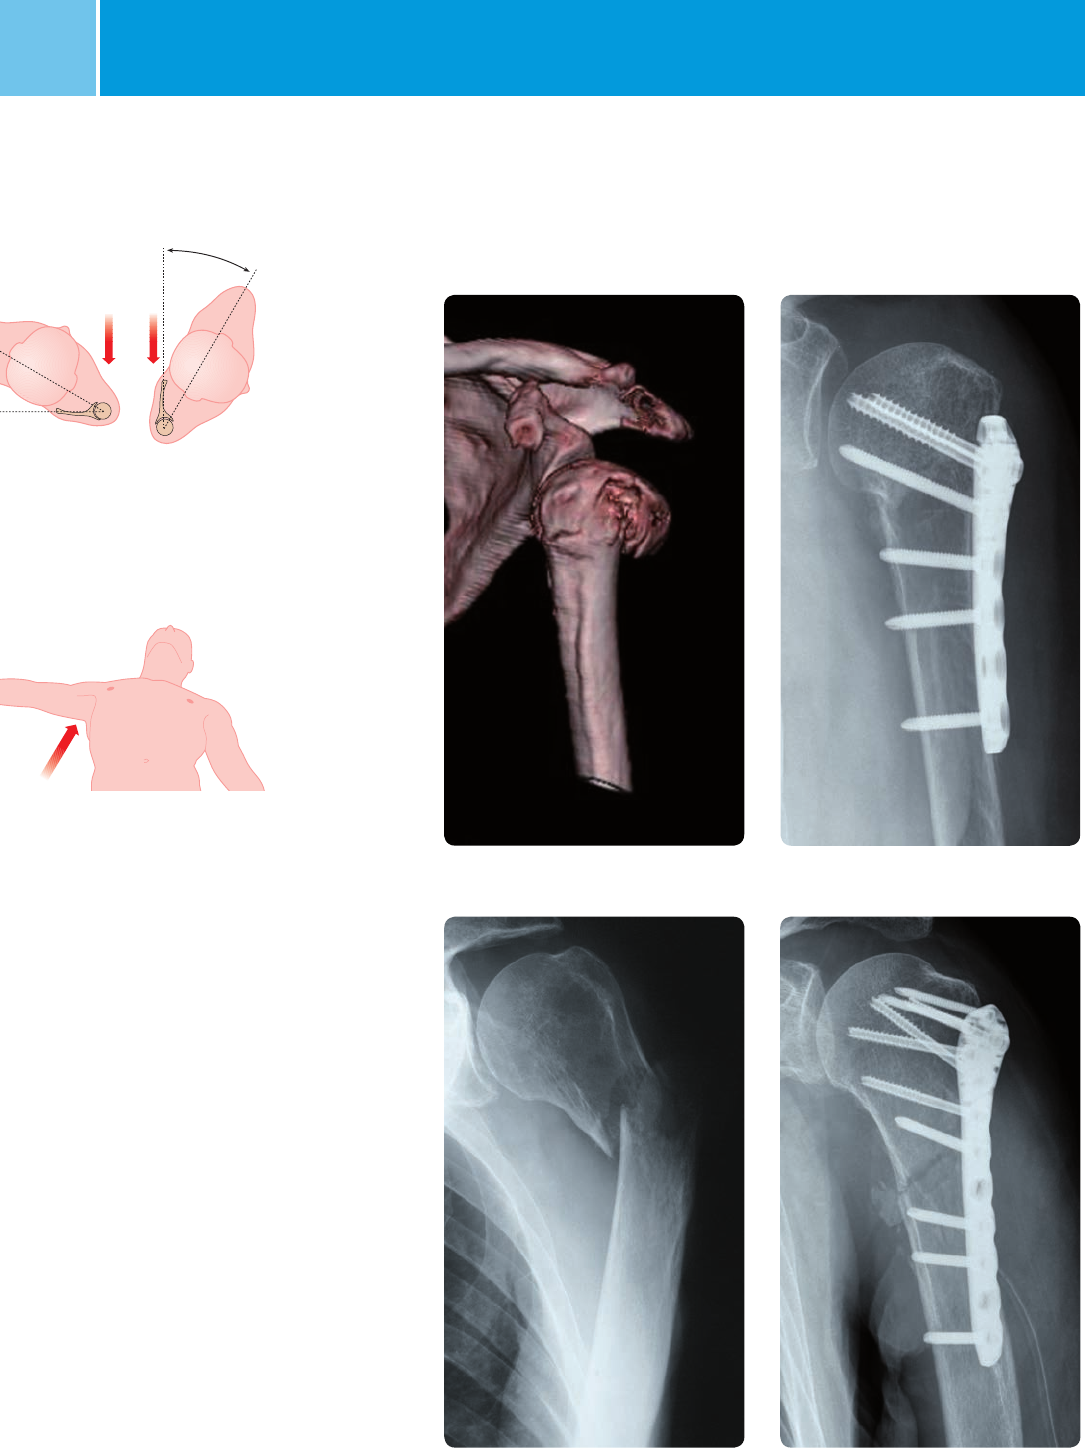

Sample Cases

Preoperative Postoperative, MIS* operation technique

Preoperative Postoperative, open operation technique

*MIS Minimally Invasive Solutions™ Technique by Zimmer